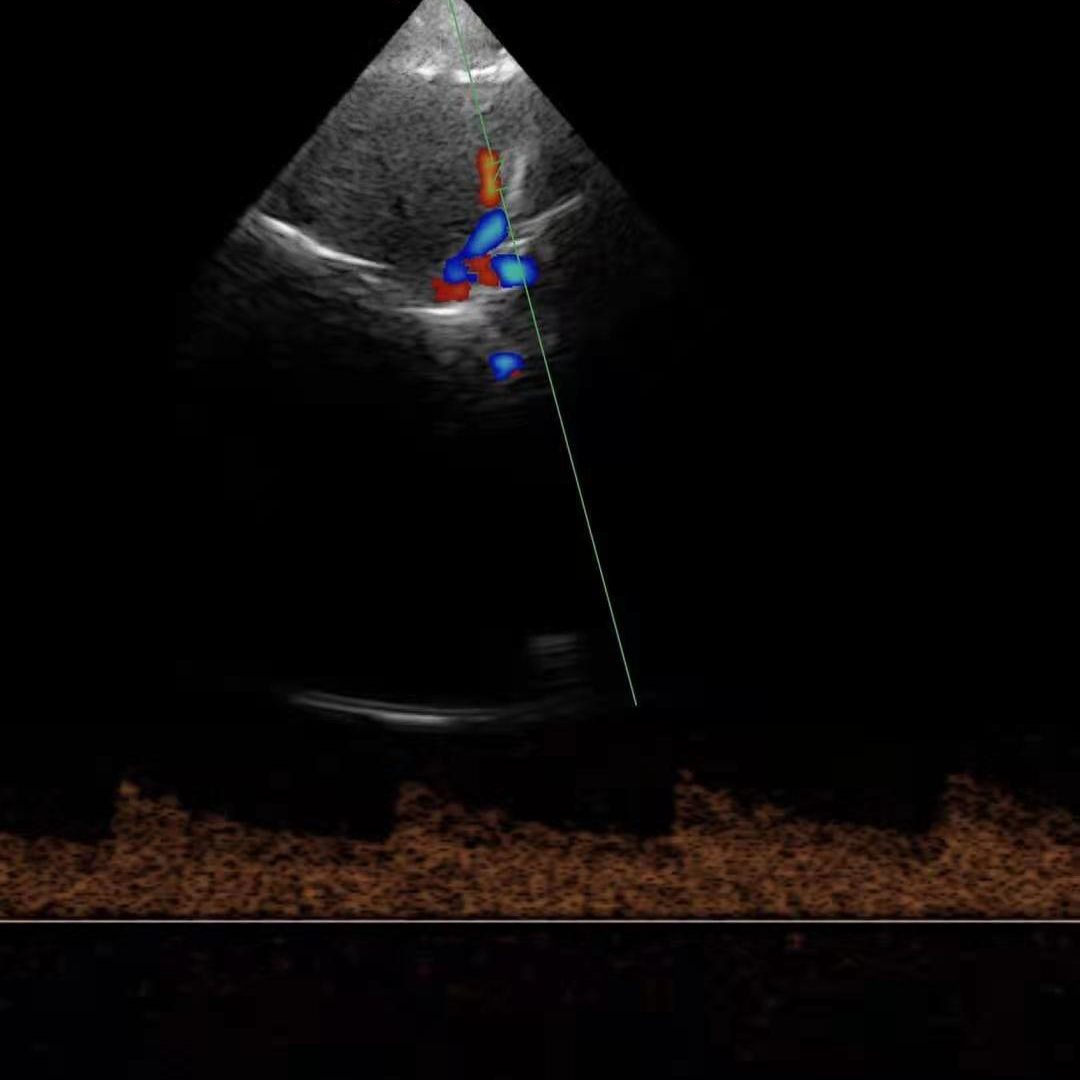

| Modo de escaneo | B, B/M, Color, PW |

Modos de escaneo: B, B/M, Color, PW

Exámenes básicos y control de flujo cardíaco o vascular en entornos clínicos y extrahospitalarios.